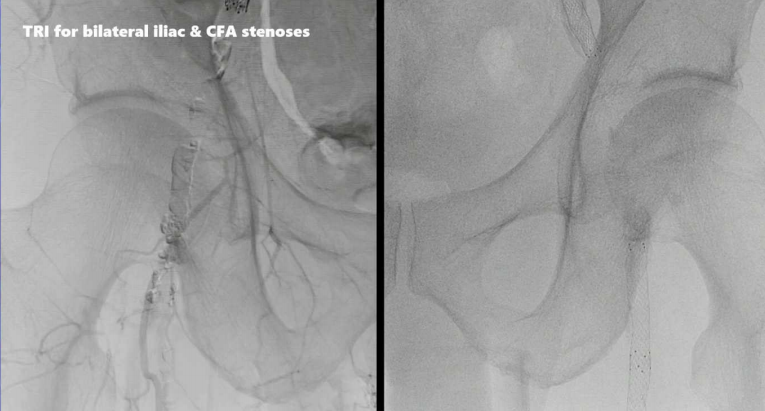

病例三:双侧髂动脉、股总动脉狭窄

经桡动脉入路,双侧髂动脉植入S.M.A.R.T. RADIANZ®支架,日本最近已上市200cm长轴药物涂层球囊(DCB),可用于TRI处理股浅动脉病变,双侧股总动脉至腘动脉近端使用DCB扩张,最终造影结果满意。